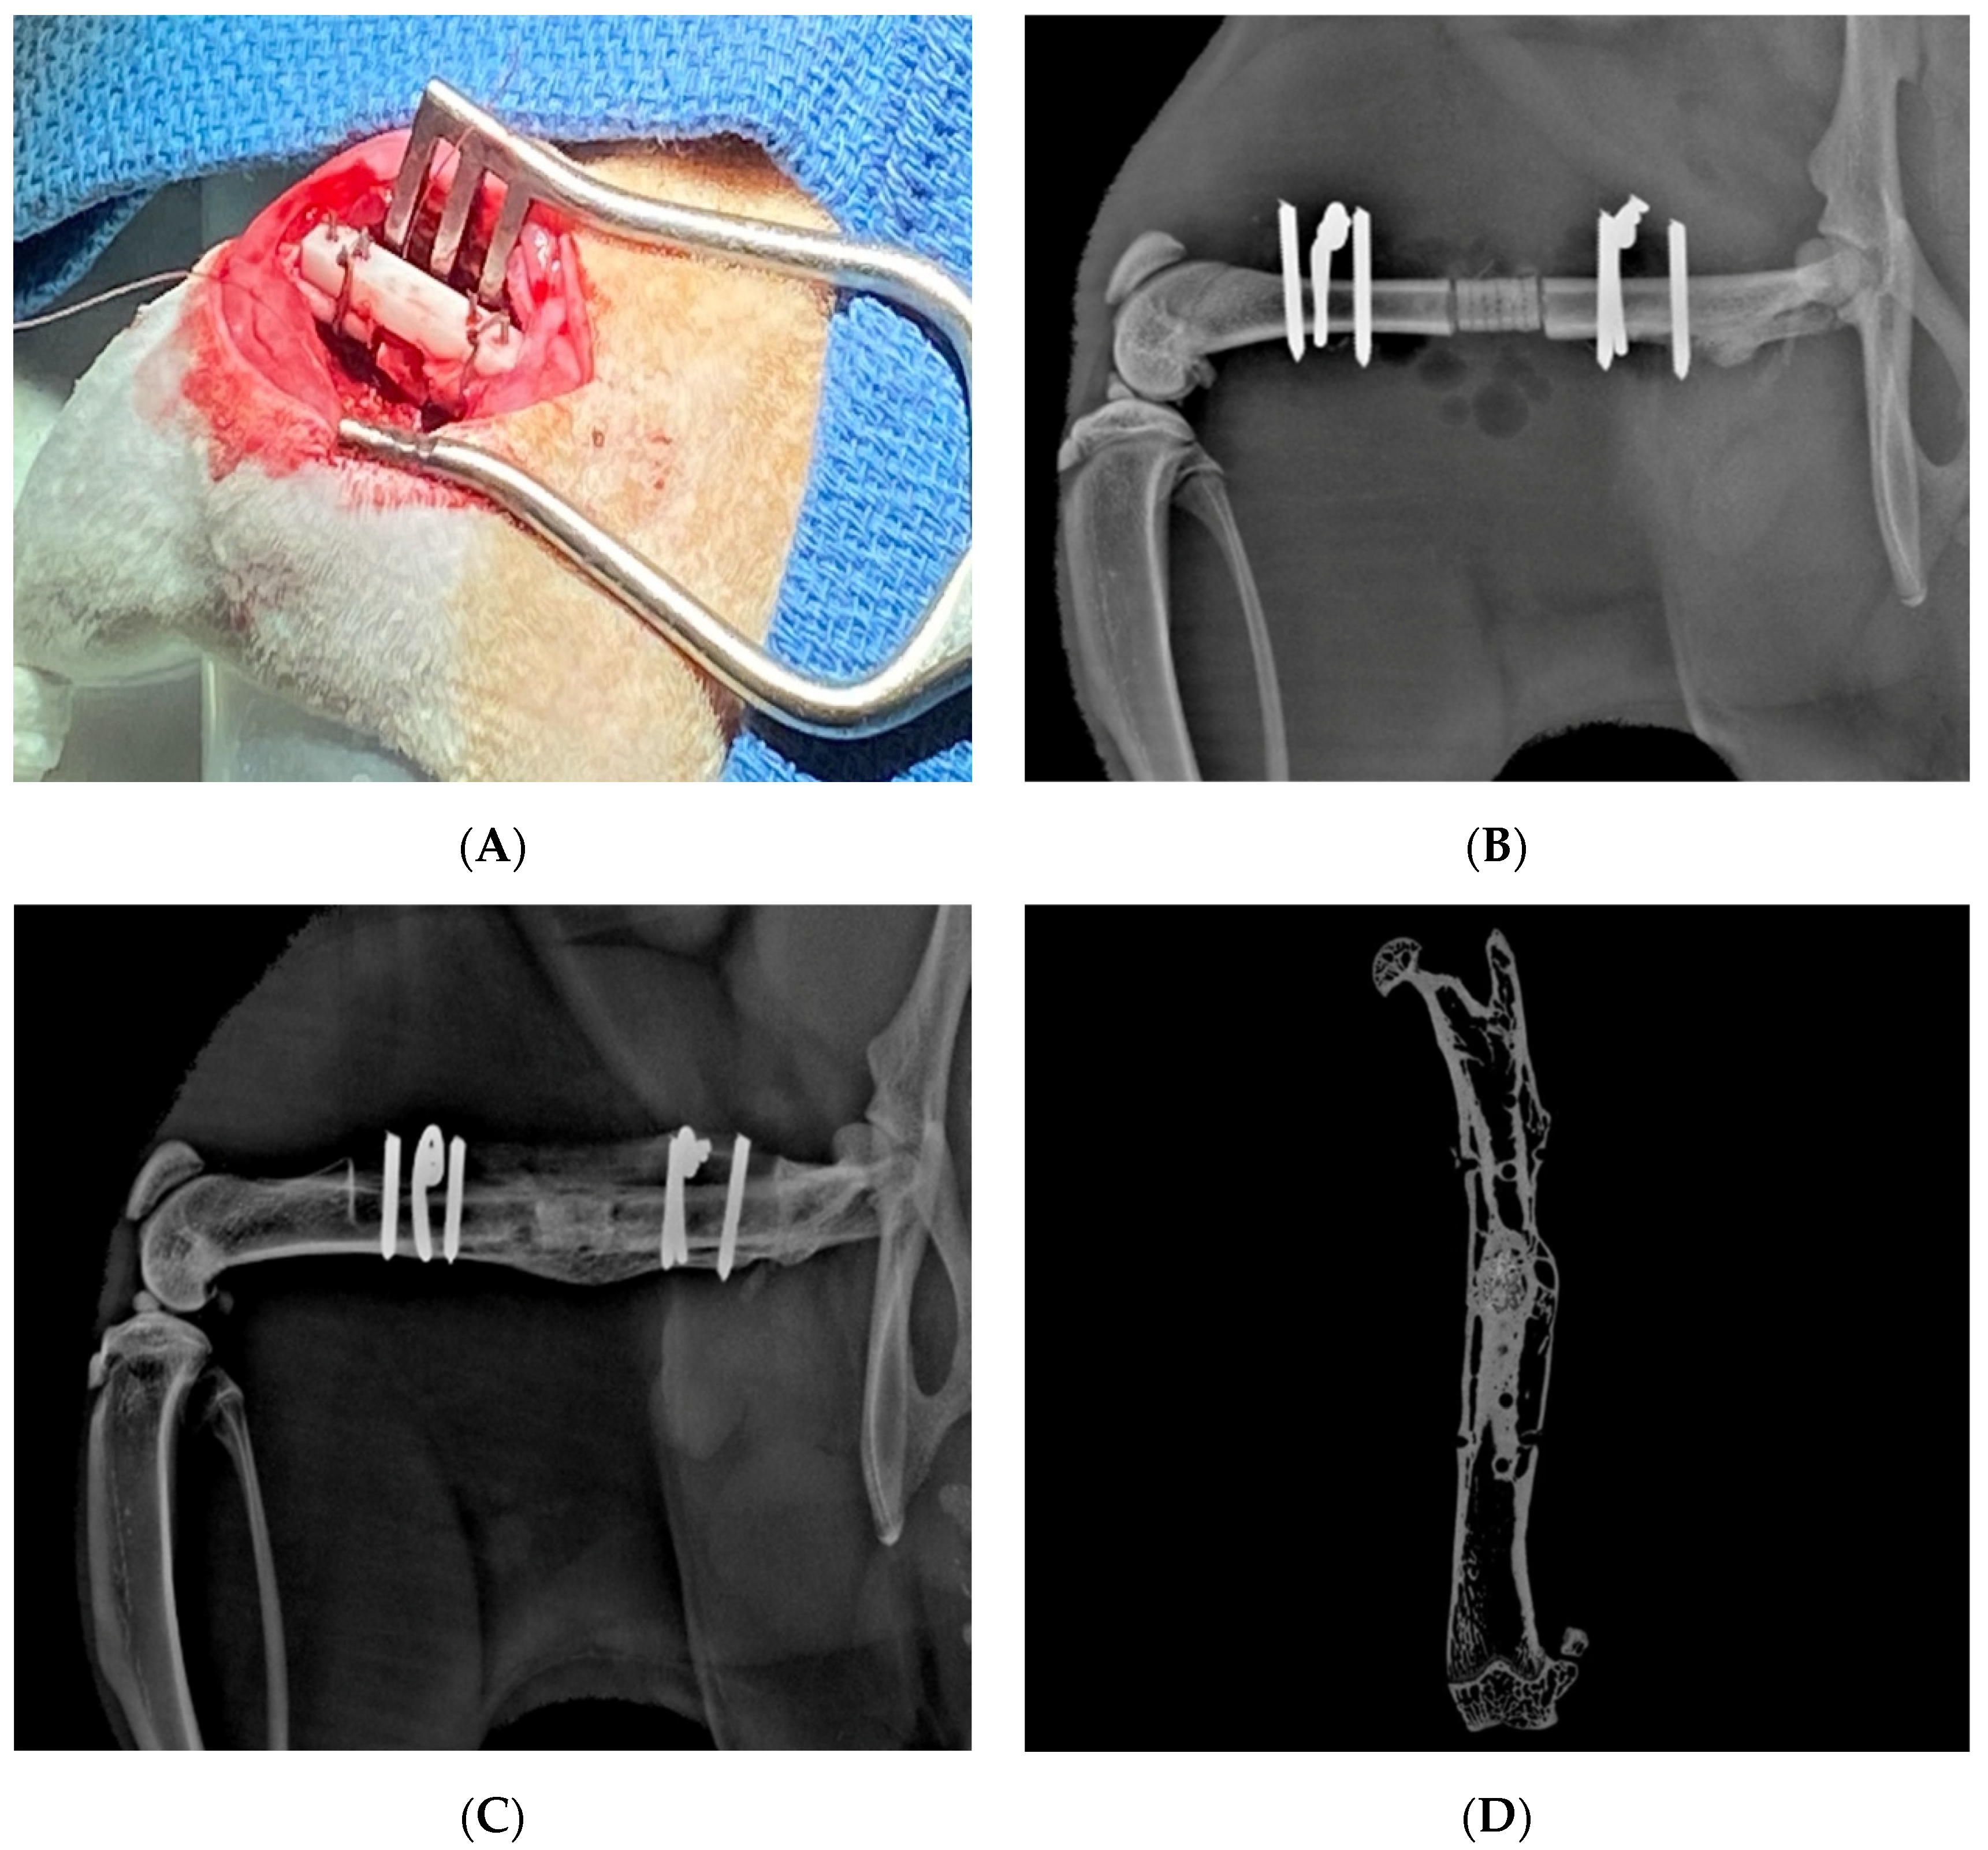

Figure 3.

Management of infected humeral shaft non-union with free vascularized fibula transfer (arrow) (A). Initially treated with removal of hardware, debridement, and temporary antibiotic cement spacer (B). Subsequently, the patient underwent vascularized free fibula transfer and revision open reduction internal fixation (C), with excellent graft incorporation at one-year follow up (D).